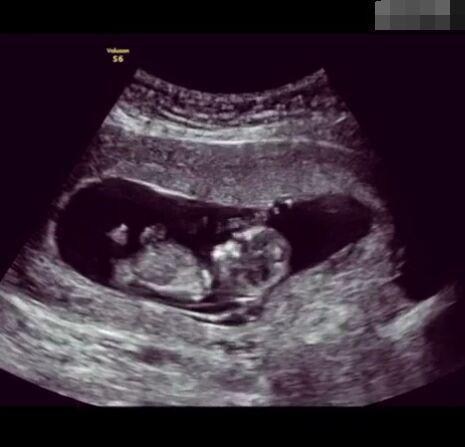

懷孕后,寶寶的性別一直是全家人的重點(diǎn)關(guān)注對(duì)象。而男女性別的差異,在基因?qū)用骟w現(xiàn)在第二十三對(duì)染色體上,如果是XY則是男孩,XX則是女孩,這都是由那枚與卵子結(jié)合的精子來決定。

圖片8.png

那些做了B超檢查確定胎兒男女,生下來后發(fā)現(xiàn)不對(duì)的,多半是因?yàn)樵贐超檢查時(shí)寶寶太調(diào)皮,以致影響了檢查準(zhǔn)確性。就比如說,有的女寶寶在媽媽肚子里玩自己的臍帶,把臍帶夾到了兩腿中間,B超就有一定幾率拍出來好像是男寶寶的特征,導(dǎo)致被誤認(rèn)為是男孩子。還有些男寶寶過分害羞,在做B超時(shí)雙腿緊緊并攏,醫(yī)生也很難判斷男女,只好大致猜測是女孩,就又造成了誤會(huì)。因此,B超亦不是萬能的。

其實(shí),不論男女都是父母的乖寶寶,不管是男孩還是女孩,都讓我們一起熱烈歡迎他們的到來吧!